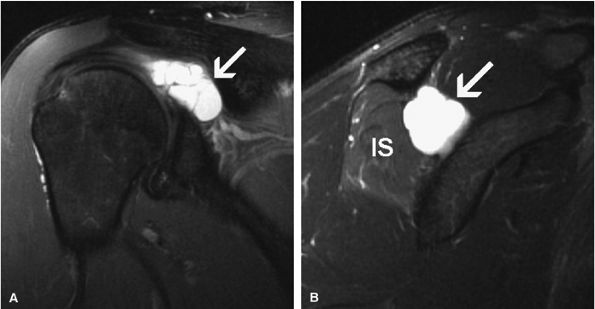

![]() |

FIGURE 12.11 ● Parsonage-Turner syndrome. Oblique sagittal T1-weighted (A) and fat-suppressed T2-weighted (B) images show denervation edema and atrophy of the infraspinatus (IS) and teres minor (arrow) muscles.